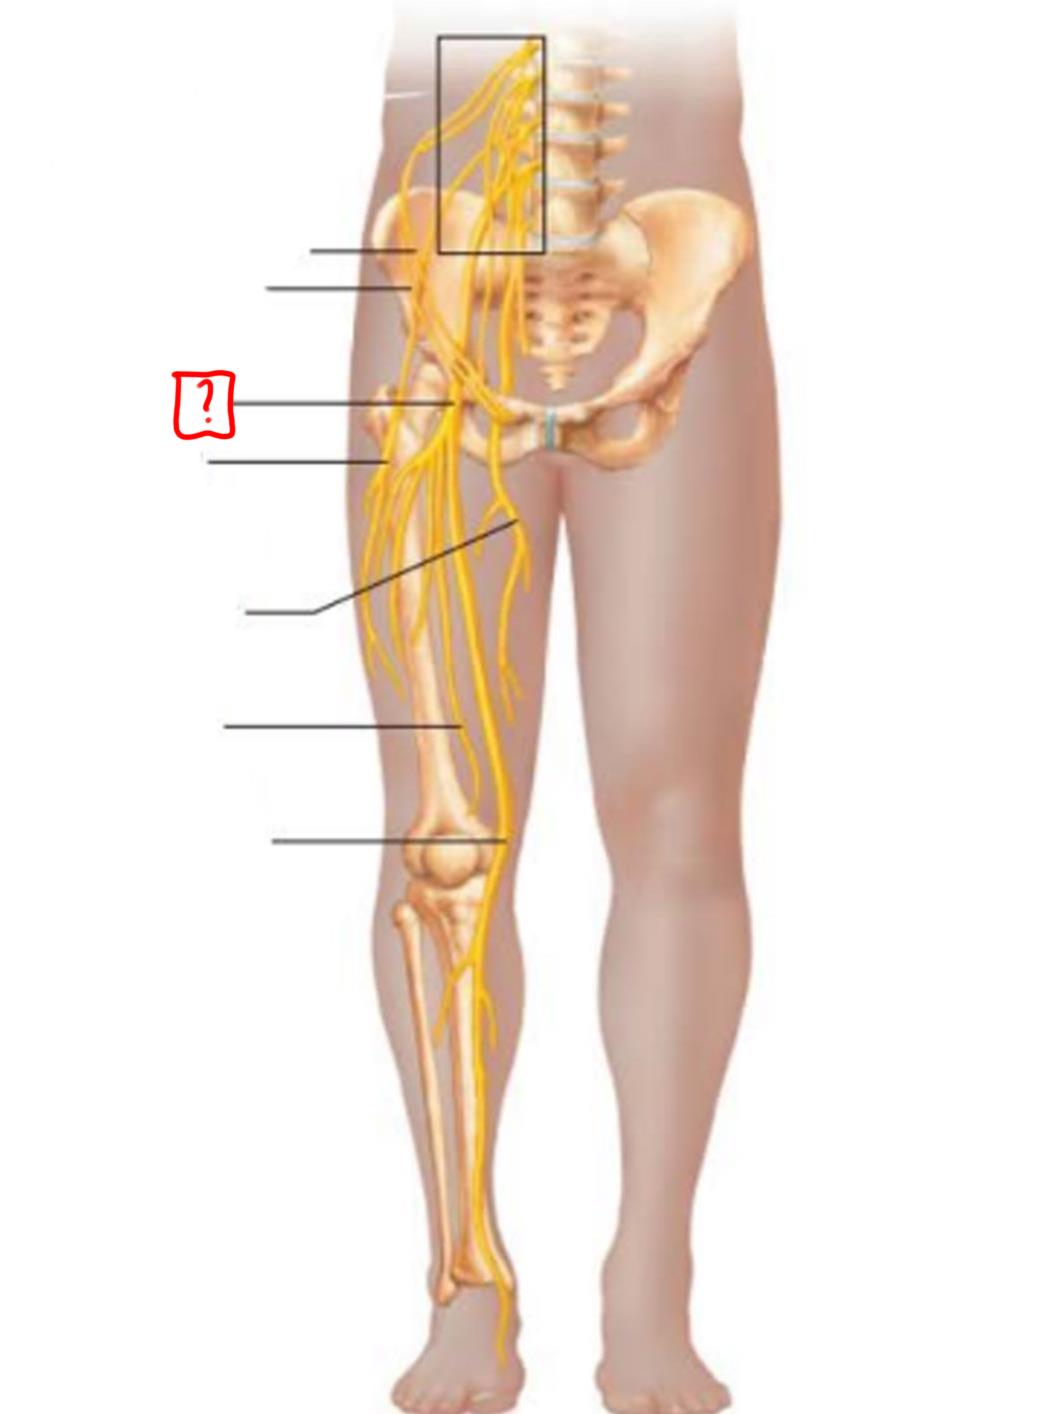

superior gluteal

inferior gluteal

pudendal

sciatic

posterior femoral cutaneous